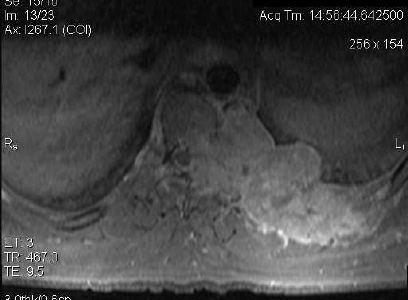

Cancer of the Spine

Cancer of the spine, both secondary and primary, are of particular interest to this practice. Dr Mobbs has undertaken further training in complex spine cancer surgery and reconstruction.

Click on the thumbnails for enlarged view